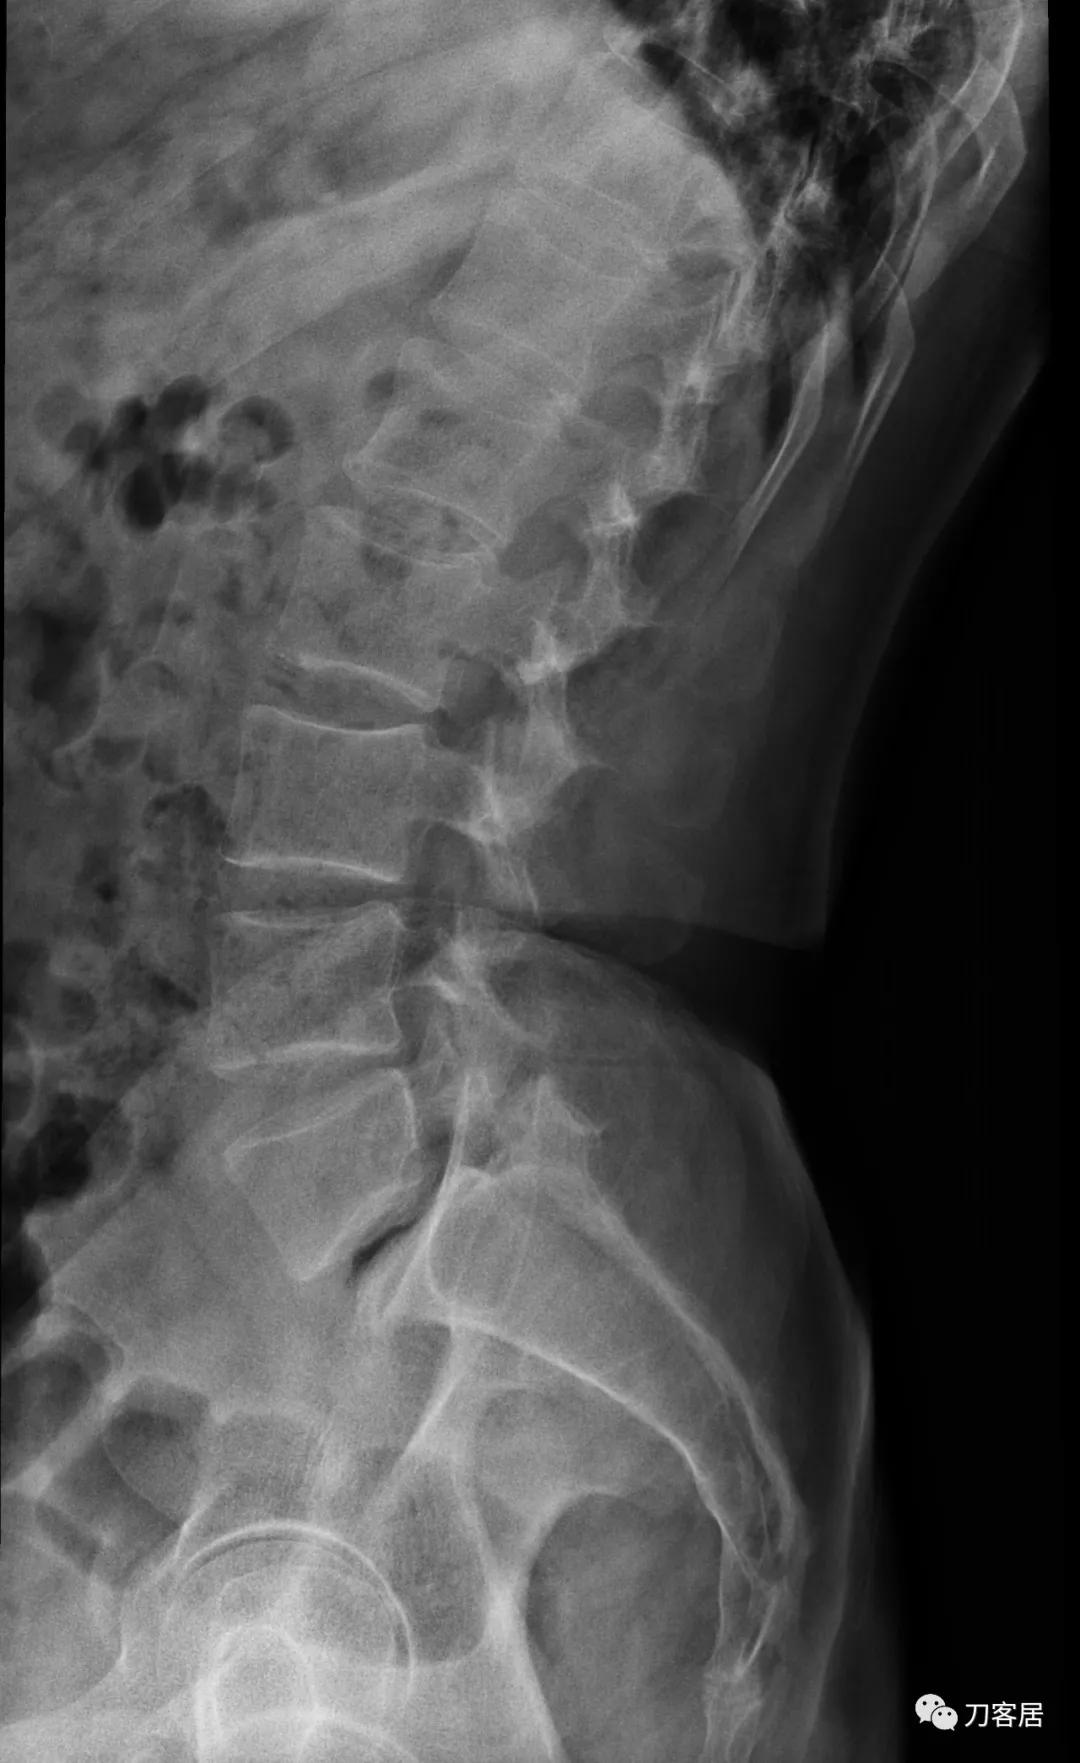

自带影像学检查提示腰5椎体前滑脱,腰5峡部裂,椎管狭窄不严重。

诊断:腰5峡部裂,腰5椎体前滑脱1度,骨质疏松症。

图5. 20210616术前腰椎过伸位X线片

图6. 20210616术前腰椎过屈位X线片